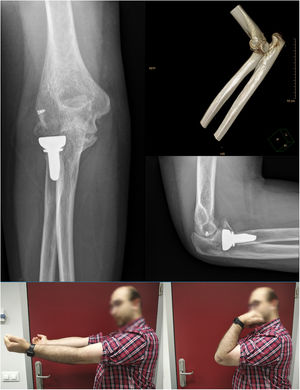

Una vez finalizada la reparación osteoligamentosa se lleva a cabo la comprobación de la estabilidad y la congruencia articular en el conjunto del arco de movilidad pasiva en flexoextensión del codo. En caso de que se encuentre una inestabilidad franca con pérdida de congruencia articular, se procederá a completar la colocación del dispositivo IJS-E según la técnica descrita por el fabricante (Imagen 3). Si, por el contrario, se obtiene una adecuada congruencia articular en el conjunto de arco de movilización pasiva en flexoextensión, así como una correcta estabilidad en el plano coronal con las maniobras de estrés varo-valgo, se procede a la extracción del pin humeral puesto que se considera que no sería necesario la aumentación con el dispositivo IJS-E.

La movilidad previa a la extracción del dispositivo fue de: flexión 110° (90 a 120°), déficit extensión 28° (25 a 30°), pronación 80° y supinación 80° (60 a 85°). Puesto que en todos los casos el arco de movilidad fue menor a 100°, previo a la extracción del material entre las 12 y 16 semanas, se llevó a cabo una MBA, aprovechando el segundo acto quirúrgico programado para la extracción. Tras la MBA, se alcanzó en todos los casos un rango de movilidad mayor a 100° de forma intraoperatoria. Únicamente, uno de los casos (caso número 2) presentó un BAA previo con un rango de movilidad menor de 70° relacionado con un déficit en la supinación de 25°. Por ello, en este caso se efectuó una artrolisis abierta consistente en capsulectomía anterior y liberación de contractura de partes blandas con inicio de rehabilitación intensiva precoz.

No obstante, en ninguno de los casos se identificó pérdida de congruencia articular, subluxación o inestabilidad persistente durante seguimiento previo a la extracción del dispositivo. Además, tampoco encontramos molestias asociadas al implante, aflojamiento o rotura del mismo previa a su extracción.

El BAA medio al final del seguimiento fue de: flexión 134° (120 a 140°), déficit extensión de 12° (5 a 20°) y pronosupinación completa. Se recogieron los resultados funcionales a través de las escalas: DASH y MEP. La puntuación DASH media fue de 11,78 puntos (4,2 a 20,6) y la puntuación MEP media fue de 94 puntos (85 a 100).

Como complicaciones añadidas al anterior caso mencionado (caso 2) que presentó rigidez, el caso 3 objetivó una osificación heterotópica grado II a los cinco meses tras seguimiento sin significación clínica (Imagen 4). En ningún paciente se identifico inestabilidad residual, incongruencia articular, infección, hematoma complicado, rotura de material o lesión neurovascular durante el seguimiento. A modo de resumen, se muestran los valores de movilidad previa a la extracción de IJS-E, tipo de reintervención y valores funcionales en la tabla 2.